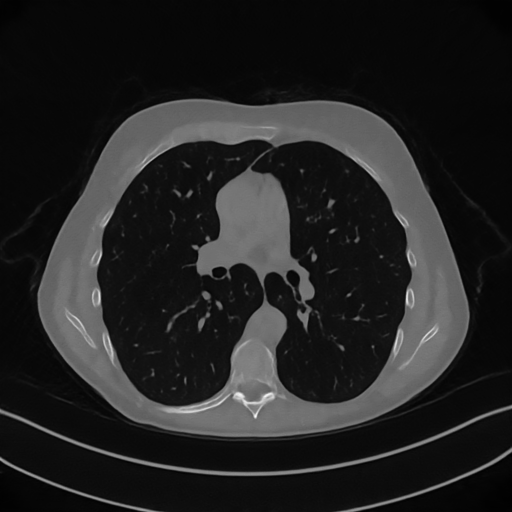

We now consider the P180,60subscript𝑃18060P_{180,60} CT protocol whose results are reported in Figure 6. In this case, the tomographic reconstruction is more challenging than in the previous experiment. The starting image xRISsubscript𝑥𝑅𝐼𝑆x_{RIS} has evident streaking artifacts and blur and some details are lost, especially in the first zoom. The artifacts are reduced in the xISsubscript𝑥𝐼𝑆x_{IS} (top right image), where some details are recovered and the edges are quite neat. The xINGsubscript𝑥𝐼𝑁𝐺x_{ING} image obtained with the proposed RISING (bottom right) is visually an excellent reconstruction. It is very similar to the xLPPsubscript𝑥𝐿𝑃𝑃x_{LPP} image, whose training, we remark, is based on more informative target images.

Figure 6: Results on a test image from the Mayo data set, under the P180,60subscript𝑃18060P_{180,60} CT protocol. Top-left: xRISsubscript𝑥𝑅𝐼𝑆x_{RIS}; top-right: xISsubscript𝑥𝐼𝑆x_{IS}; bottom-left: xLPPsubscript𝑥𝐿𝑃𝑃x_{LPP}; bottom-right: xINGsubscript𝑥𝐼𝑁𝐺x_{ING}.

In Figure 7 we plot for these experiments, the same profiles of Figure 5. In the left graph, we analyse the performance of LPP approach: the xLPPsubscript𝑥𝐿𝑃𝑃x_{LPP} reconstruction gets values quite close to the GT, but it does not fit well the target black line. In the right graph, we analyse the performance of RISING approach: the xINGsubscript𝑥𝐼𝑁𝐺x_{ING} solution almost overlaps the target xISsubscript𝑥𝐼𝑆x_{IS} profile, confirming that the network has correctly learned.